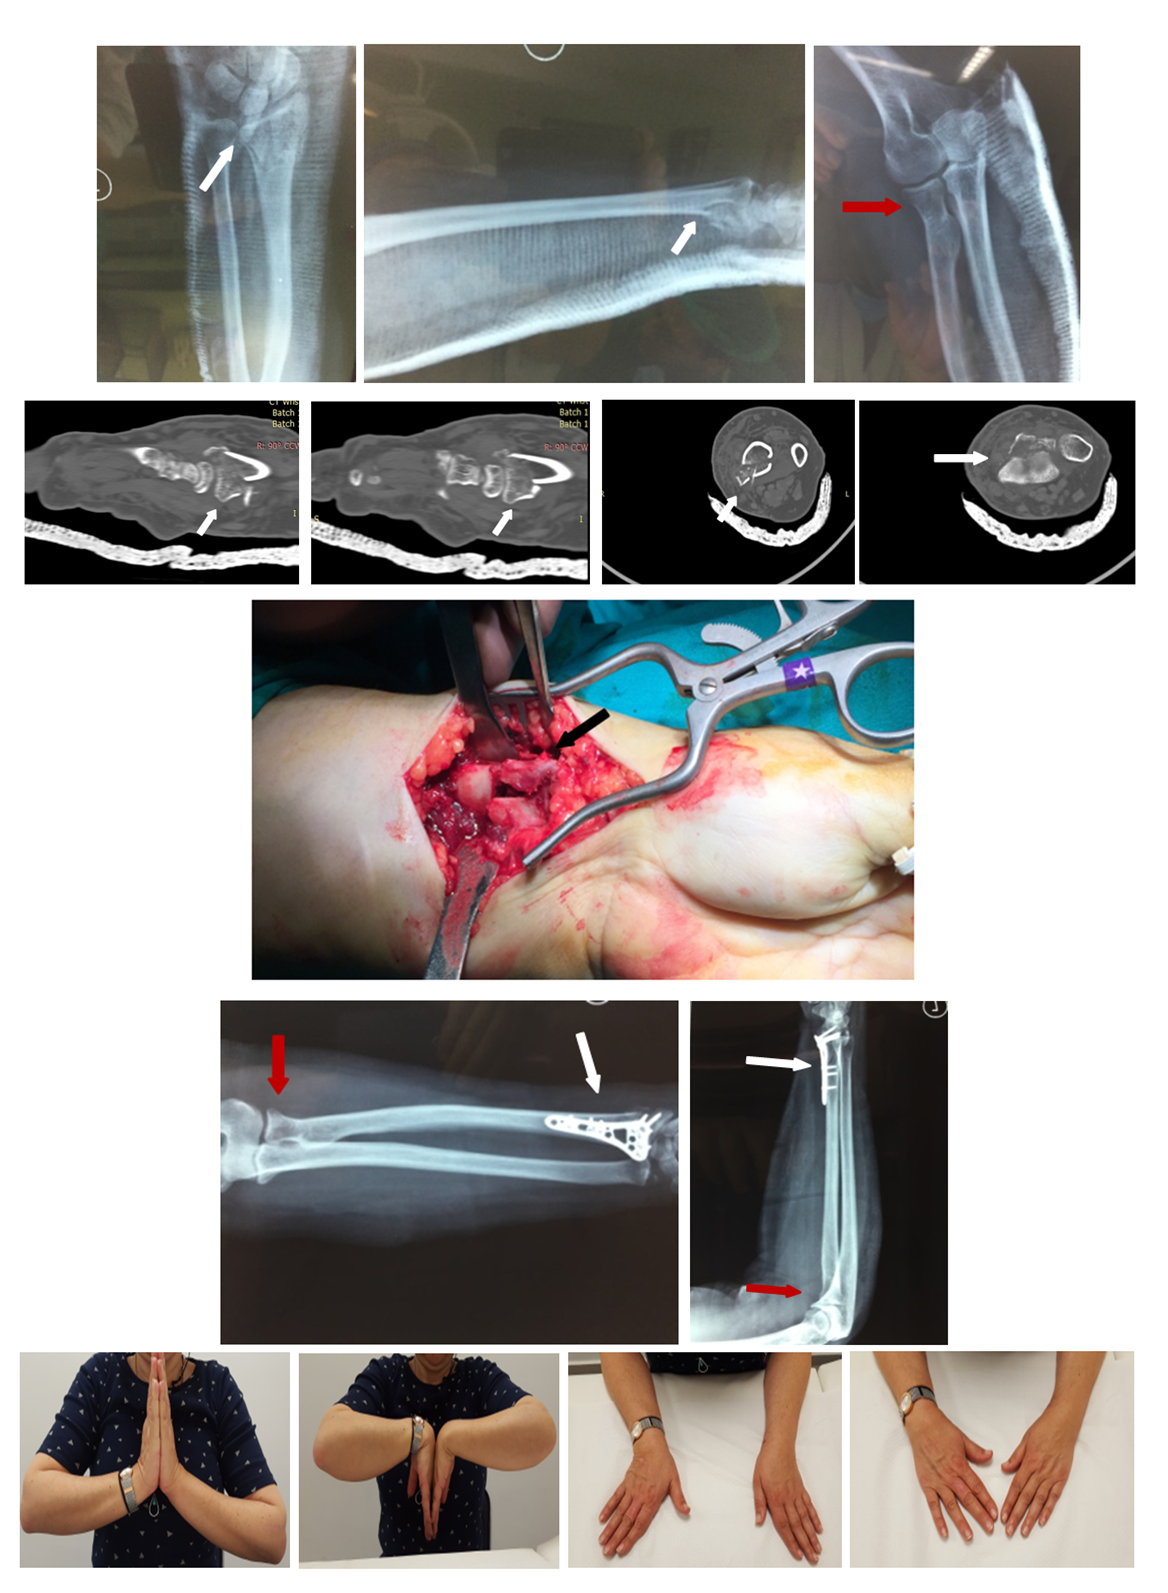

Open AccessCase Report

Simultaneous Fractures of Proximal and Distal End of Radius. An Unusual Pattern of Complex Injuries and Clinical Review

Kastanis G, Spyrantis M., Magarakis G., Kapsetakis P., Pantouvaki A.

International Journal of Innovative Research in Medical Science·September 27, 2019